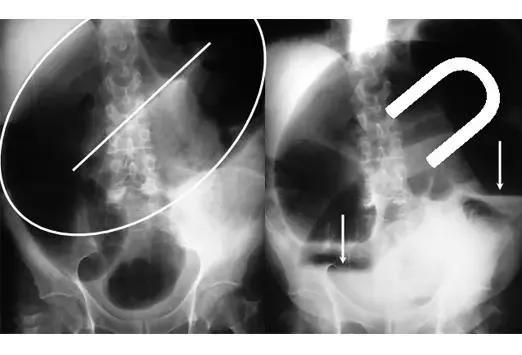

在缺血性结肠炎的诊断中,X光片也有其独特价值。一位65岁男性患者的腹部X光片显示近端小肠梗阻,同时箭头指向的“拇指纹”征象,这是粘膜水肿的非特异性表现,可见于缺血性结肠炎等疾病。这种X光表现虽然不具特异性,但结合临床症状可以为诊断提供重要线索。